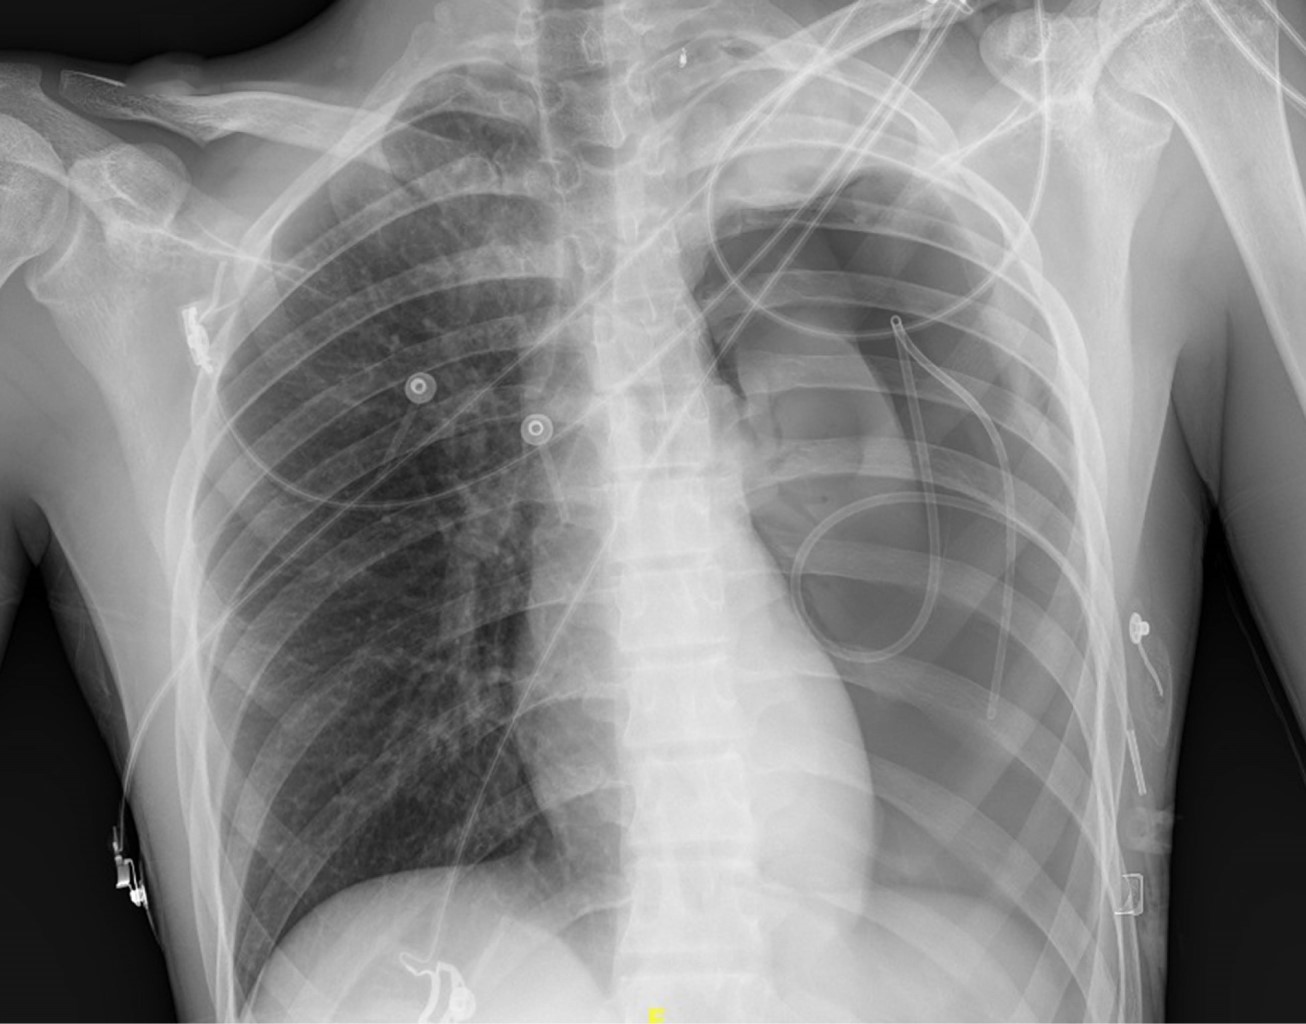

A la exploración física (EF) se encuentra con constantes vitales dentro de la normalidad, con buena saturación. Se destaca hipofonesis en región anterior de ápex pulmonar izquierdo, por lo que se realiza una radiografía de tórax en la que se aprecia un neumotórax izquierdo del 15% (Figura 1) según el índice de Light. El electrocardiograma y exámenes de laboratorio fueron normales.

Figura 1